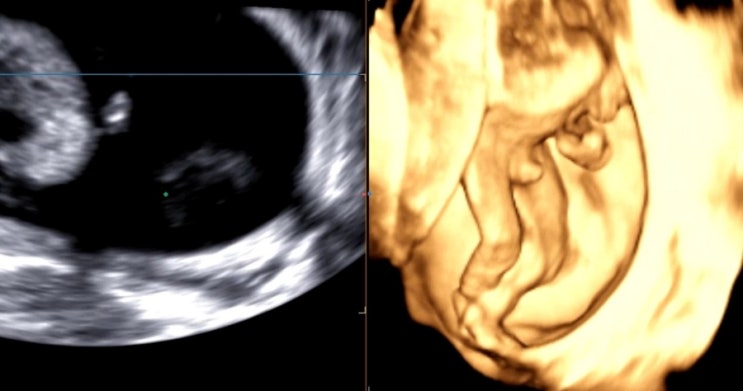

내가 또... 둘째 임신. 8개월치 일기

24년 9월 28일 임신테스트기 두 줄을 확인하고 써내려간 약 8개월간의 일기 시작합니다 ͙͘͡★ 우리 가족...